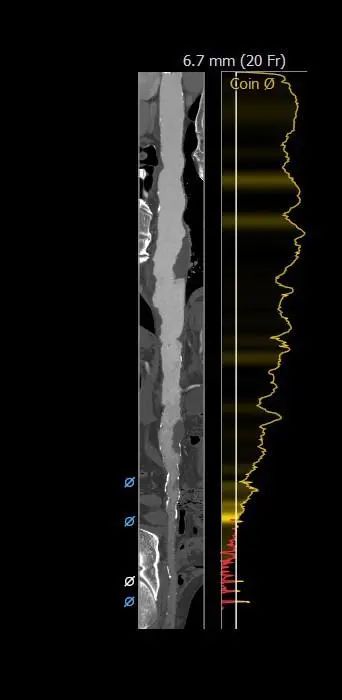

主动脉根部评估

根部概览

瓣上分析&心室大小分析

外周分析